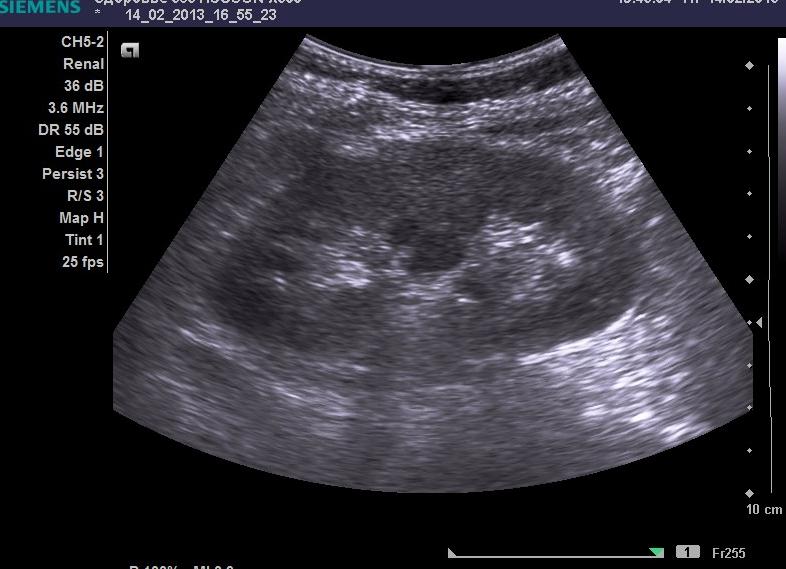

Множество заболеваний диагностируются сегодня при помощи ультразвукового оборудования. Говоря про обследование органов брюшной полости, отмечено, что пациенты легко переносят процедуру, подготовка к которой не является слишком сложной. Это относится и к УЗИ почек. Благодаря своевременному обследованию, можно выявить наличие камней, кисту, проблемы сосудов, опухоли на ранней стадии развития и принять необходимые меры по лечению заболеваний. Однако даже столь простая процедура требует качественной предварительной работы. О том, как подготовиться к узи почек, подробно рассмотрено далее.

Неоспоримым достоинством ультразвукового исследования выступает отсутствие побочных эффектов. Это создает возможность проводить исследование с такой периодичностью, которая позволит отследить отступление болезни. Анализ состояния почек с помощью УЗИ не только выявляет болезни — также он является подготовительным этапом перед компьютерной томографией.